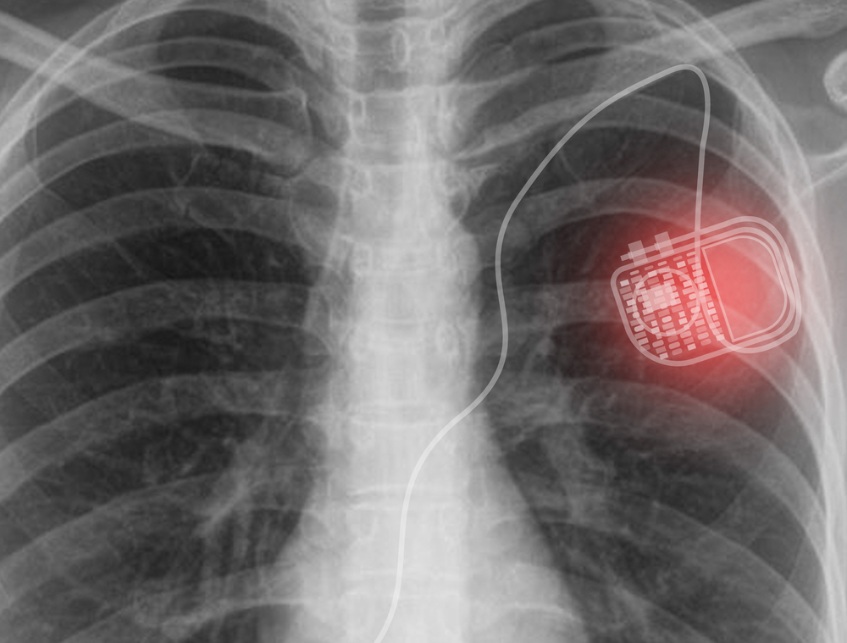

Đối với người bị nhịp tim chậm lâu năm hoặc thường xuyên, máy tạo nhịp tim lâu dài là phương pháp tốt nhất để điều trị. Điều này hiệu quả với các tình trạng như hội chứng suy nút xoang (khi các tế bào tạo nhịp nhịp tim tự nhiên không hoạt động bình thường).

Mặc dù máy tạo nhịp tim vĩnh viễn không thể chữa trị dứt điểm hoàn toàn bệnh nhưng nó có thể là giải pháp lâu dài để kiểm soát tình trạng nhịp tim dưới 60 và ngăn chặn biến chứng nghiêm trọng hơn. Hầu hết các máy tạo nhịp tim đều có thể sử dụng trong vài năm, một số khác có thể kéo dài cả một thập kỷ.

Việc sử dụng máy tạo nhịp tim lâu dài cần đến phẫu thuật để cấy ghép thiết bị, thiết bị này sẽ cung cấp xung điện cho cơ tim. Trong quá trình đặt máy, bác sĩ phẫu thuật sẽ tạo một túi nhỏ dưới da để đặt máy tạo nhịp. Sau đó, họ sẽ đặt và kết nối các dây dẫn vào các điểm khác nhau trên tim của người bệnh.

Việc cấy ghép máy tạo nhịp tim có thể tránh được phẫu thuật thông thường. Đó là bởi vì có các máy điều hòa nhịp tim không dây mới hơn dành cho chứng rối loạn nhịp tim chậm được cấy ghép bằng thủ thuật dựa trên ống thông. Thủ thuật này sử dụng một dây dẫn được đưa vào qua các động mạch. Sau đó, luồng vào tim, nơi họ có thể cấy máy điều hòa nhịp tim trực tiếp vào bên trong. Những thiết bị này rất nhỏ và người bệnh có thể về nhà sớm hơn nhiều so với khi phẫu thuật.